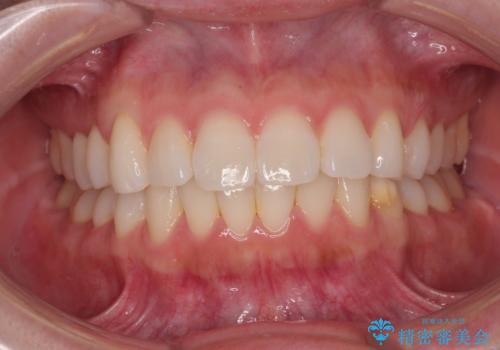

- インビザライン・モデレート

- 11ヶ月

- 2-5回